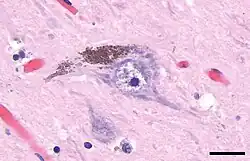

Клетки этой субстанции богаты одной из форм природного пигмента меланина — нейромеланином, который и придаёт ей характерный тёмный цвет. В чёрной субстанции различают дорсально расположенный компактный слой (pars compacta) и вентральный (pars reticulata) — сетчатый слой[6]. Pars compacta лежит медиальнее pars reticulata. Иногда упоминается и третий латеральный слой — pars lateralis, хотя его обычно классифицируют как часть pars reticulata. Pars reticulata и внутренняя часть бледного шара разделяются внутренней капсулой[7].

Болезнь Паркинсона является нейродегенеративным заболеванием, характеризующимся гибелью дофаминергических нейронов в pars compacta чёрной субстанции, причины, которой до сих пор неизвестны. Для болезни Паркинсона характерны двигательные нарушения: тремор, гипокинезия, мышечная ригидность, постуральная неустойчивость, а также вегетативные и психические расстройства[16] — результат снижения тормозящего влияния бледного шара (globus pallidus), расположенного в переднем отделе головного мозга, на полосатое тело (striatum). Повреждение нейронов паллидума приводит к «торможению торможения» периферических двигательных нейронов[16] (мотонейронов спинного мозга). На данный момент болезнь неизлечима, однако существующие методы консервативного и оперативного лечения позволяют значительно улучшить качество жизни больных[16]. С помощью позитронно-эмиссионной томографии доказано, что темпы дегенерации нейронов чёрной субстанции при болезни Паркинсона намного выше, чем при нормальном старении[17].